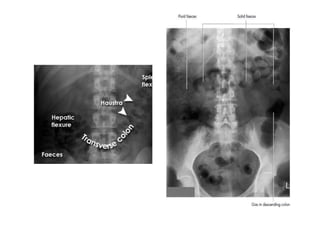

• Large bowel

• The retroperitoneal structures of the colon (ascending colon,

descending colon, and rectum) are relatively constant in position.

These are often more readily identified than the transverse colon or

sigmoid colon which are more variable in position. If visible, the

caecum is often the widest segment. It too has a variable position,

but is most often confined to the right iliac fossa.

• The longitudinal muscles (taenia coli) and circular muscles of the

colon form sacculations called haustra, which have characteristic

radiographic appearance.

• Another characteristic feature of large bowel is that it contains

faeces. This has a mottled appearance due to its part gaseous

content.